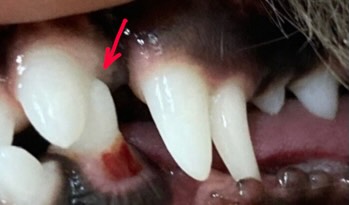

歯周疾患診療

人と同じように犬猫も口腔内環境が重要です。